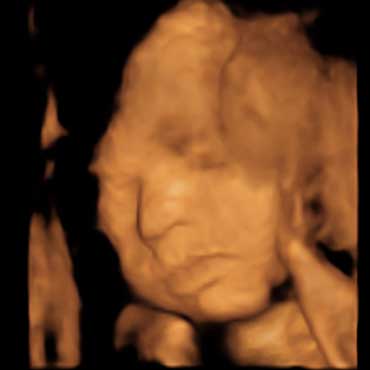

All photos are from our equipment and are of our actual clients.